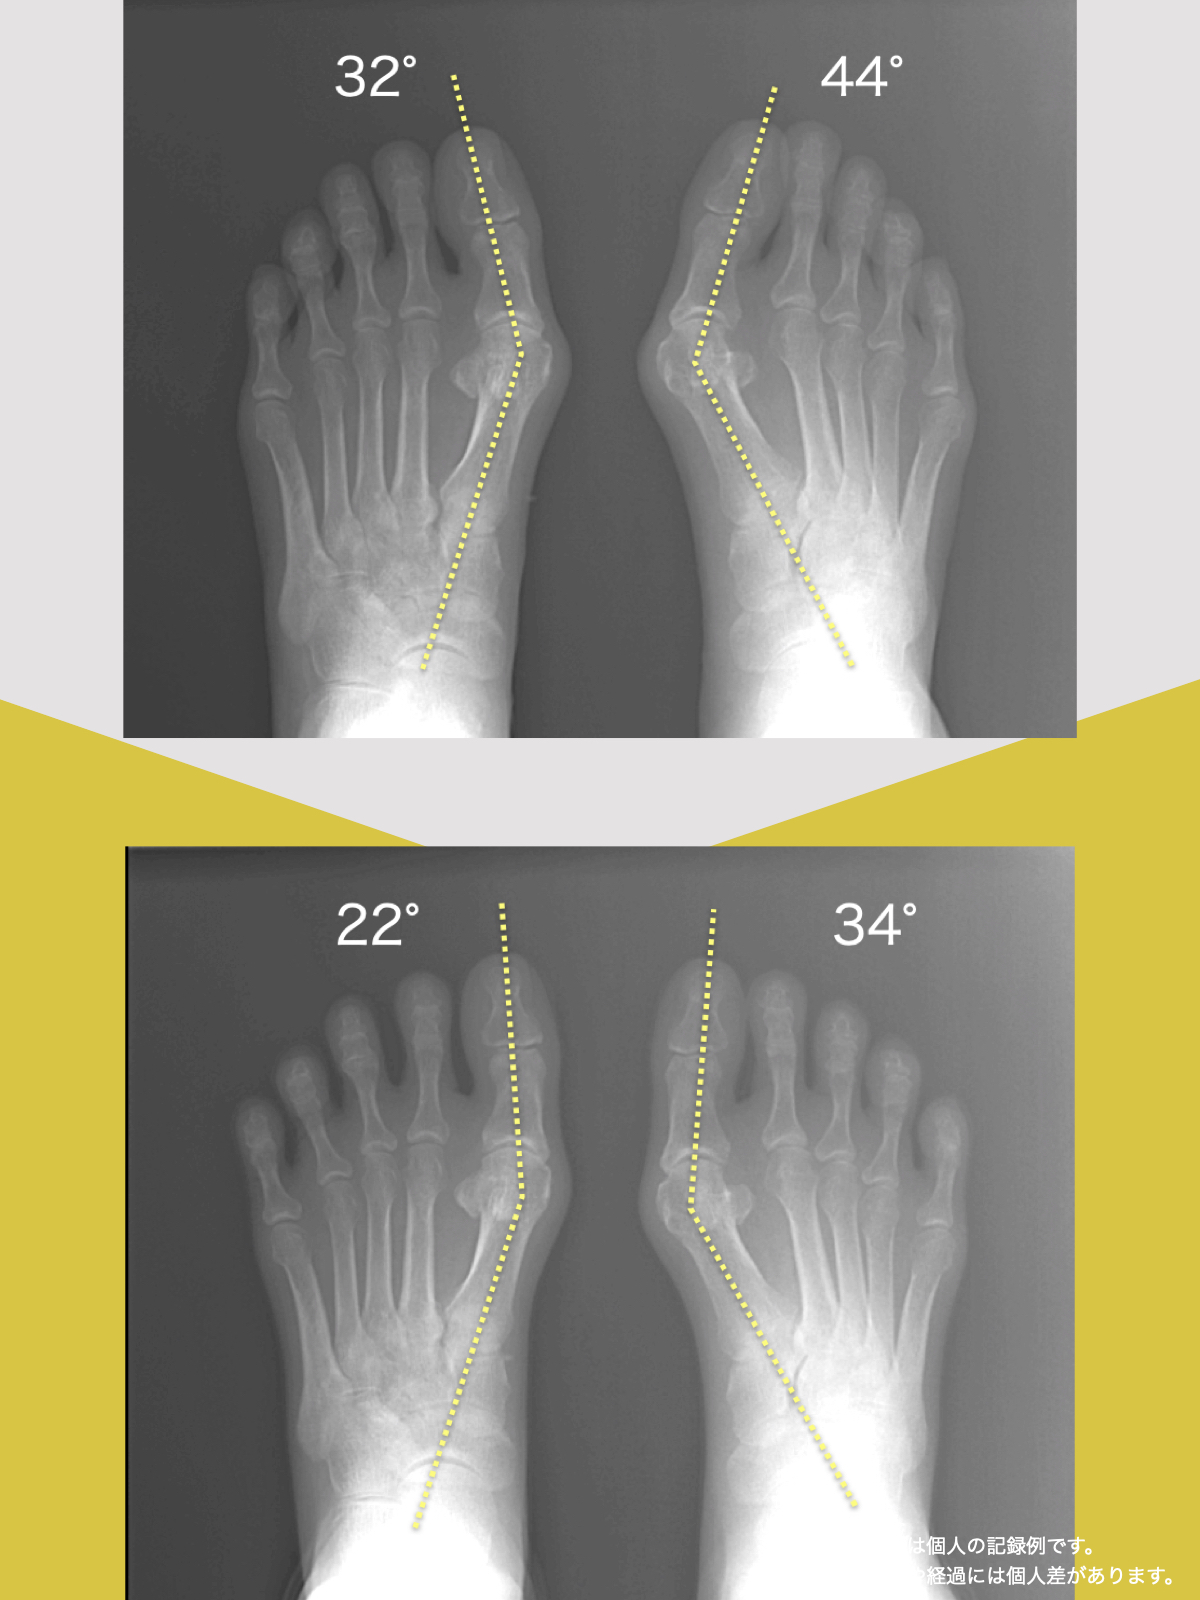

机上の理論ではない

結果こそが全て

それがYOSHIRO SOCKSです。

10年以上の臨床と観察から

実際に見えてきた足と姿勢の変化です。

外反母趾・内反小趾・浮き指・屈み指・寝指。

これらは単なる足指の問題ではありません。

足指が使えなくなると、重心がずれ、姿勢はゆがみ、膝・腰・首へ負担が連鎖します。

つまり、足指の変形は全身のゆがみのスタート地点なのです。

外反母趾